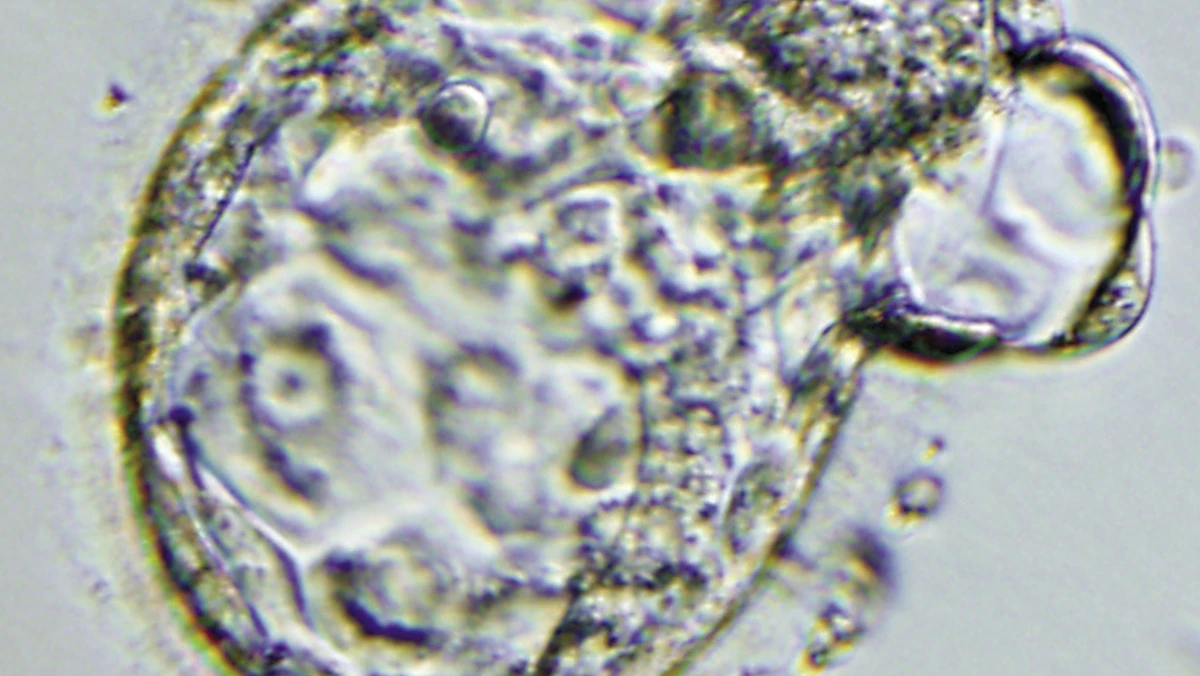

كما أوضحت المبادئ الأساسية للتطور المبكر باستخدام نموذج جنيني قائم على الخلايا الجذعية يُعرف باسم "البلاستويدات"، إذ كان الأمر مبهماً في المرحلة المبكرة من التطور، عندما تكون الكيسة الأريمية (تكوين مبكر يحوي الخلايا الجنينية الأولية والتي تُشكل المشيمة فيما بعد)، قبل أن تقوم المشيمة والرحم برعاية الجنين وإيوائه.

وتعتبر "البلاستويدات" نماذج في المختبر من الكيسة الأريمية، وهي جنين الثدييات في الأيام القليلة الأولى بعد الإخصاب.

وتم تطوير نماذج الأجنة هذه لأول مرة من الخلايا الجذعية للفأر، ثم من الخلايا الجذعية البشرية، وتوفر "البلاستويدات" بديلاً أخلاقياً لاستخدام الأجنة في البحث، والأهم من ذلك أنها تتيح اكتشافات متعددة.